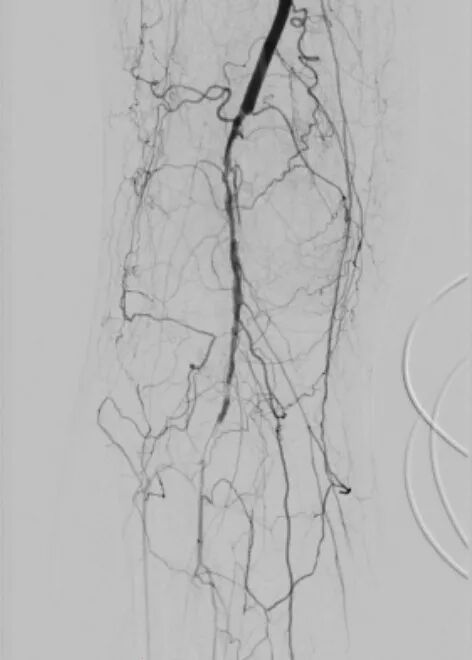

第一个病例中,患者因下肢严重缺血入院。术前常规血管造影提示为“动脉闭塞”。如果按照传统思路,需要直接实施球囊扩张加支架植入手术。为实现精准诊疗,血管外科团队决定启用IVUS进行血管腔内探查。

IVUS探头进入血管后,病变真相清晰呈现。血管内并非预想的慢性动脉硬化斑块,而是大块脱落的血栓堵塞了血管。患者属于急性或亚急性栓塞,与慢性闭塞的治疗方案截然不同,原本的支架方案必须推翻。

术中抽栓正是基于这一精准诊断,团队迅速调整治疗策略,采用Straub-Rotarex血栓切除系统实施精准抽栓治疗。该系统如同血管内的“吸尘器”,能够将血栓碎屑彻底吸出,无需植入支架。

术后患者下肢静息痛即刻消失,血管血流恢复通畅。这一治疗既规避了盲目植入支架可能引发的远期再狭窄风险,也真正做到了“因病施治、精准施策”。